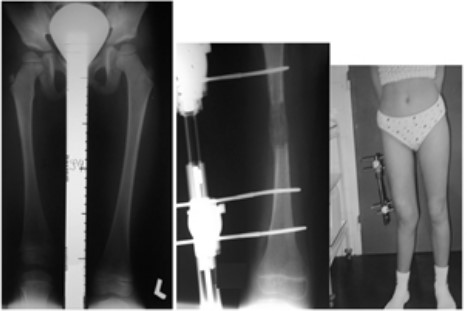

Galerija 1 Osnovne informacijeO namaDjelatnostiPreporuka za VasKako do nasPovoljna cijena ortopedskih pregledaGostovanje u emisiji Bez uputniceVažnost ultrazvučnog pregleda dječjih kukovaGalerija 1Galerija 2Galerija 3.1.Galerija 3.2.Galerija 4Galerija 5Cerebralna Paraliza i Ortopedske IntervencijeKako se pripremiti za manji operacijski zahvatSavjeti ortopeda za najčešće sportske ozljede i njihova prevencijaKralježnica: Važnost ranog prepoznavanja deformiteta i bolesti kralježniceKoljenski zglob: Razlozi brzog trošenja hrskavice, čestog ozljeđivanja i mogućnosti liječenjaPonude i popustiKarta - kako do nas?KomentariKontakt Galerija 1 Objavljeno: 18.9.2023. 15:20